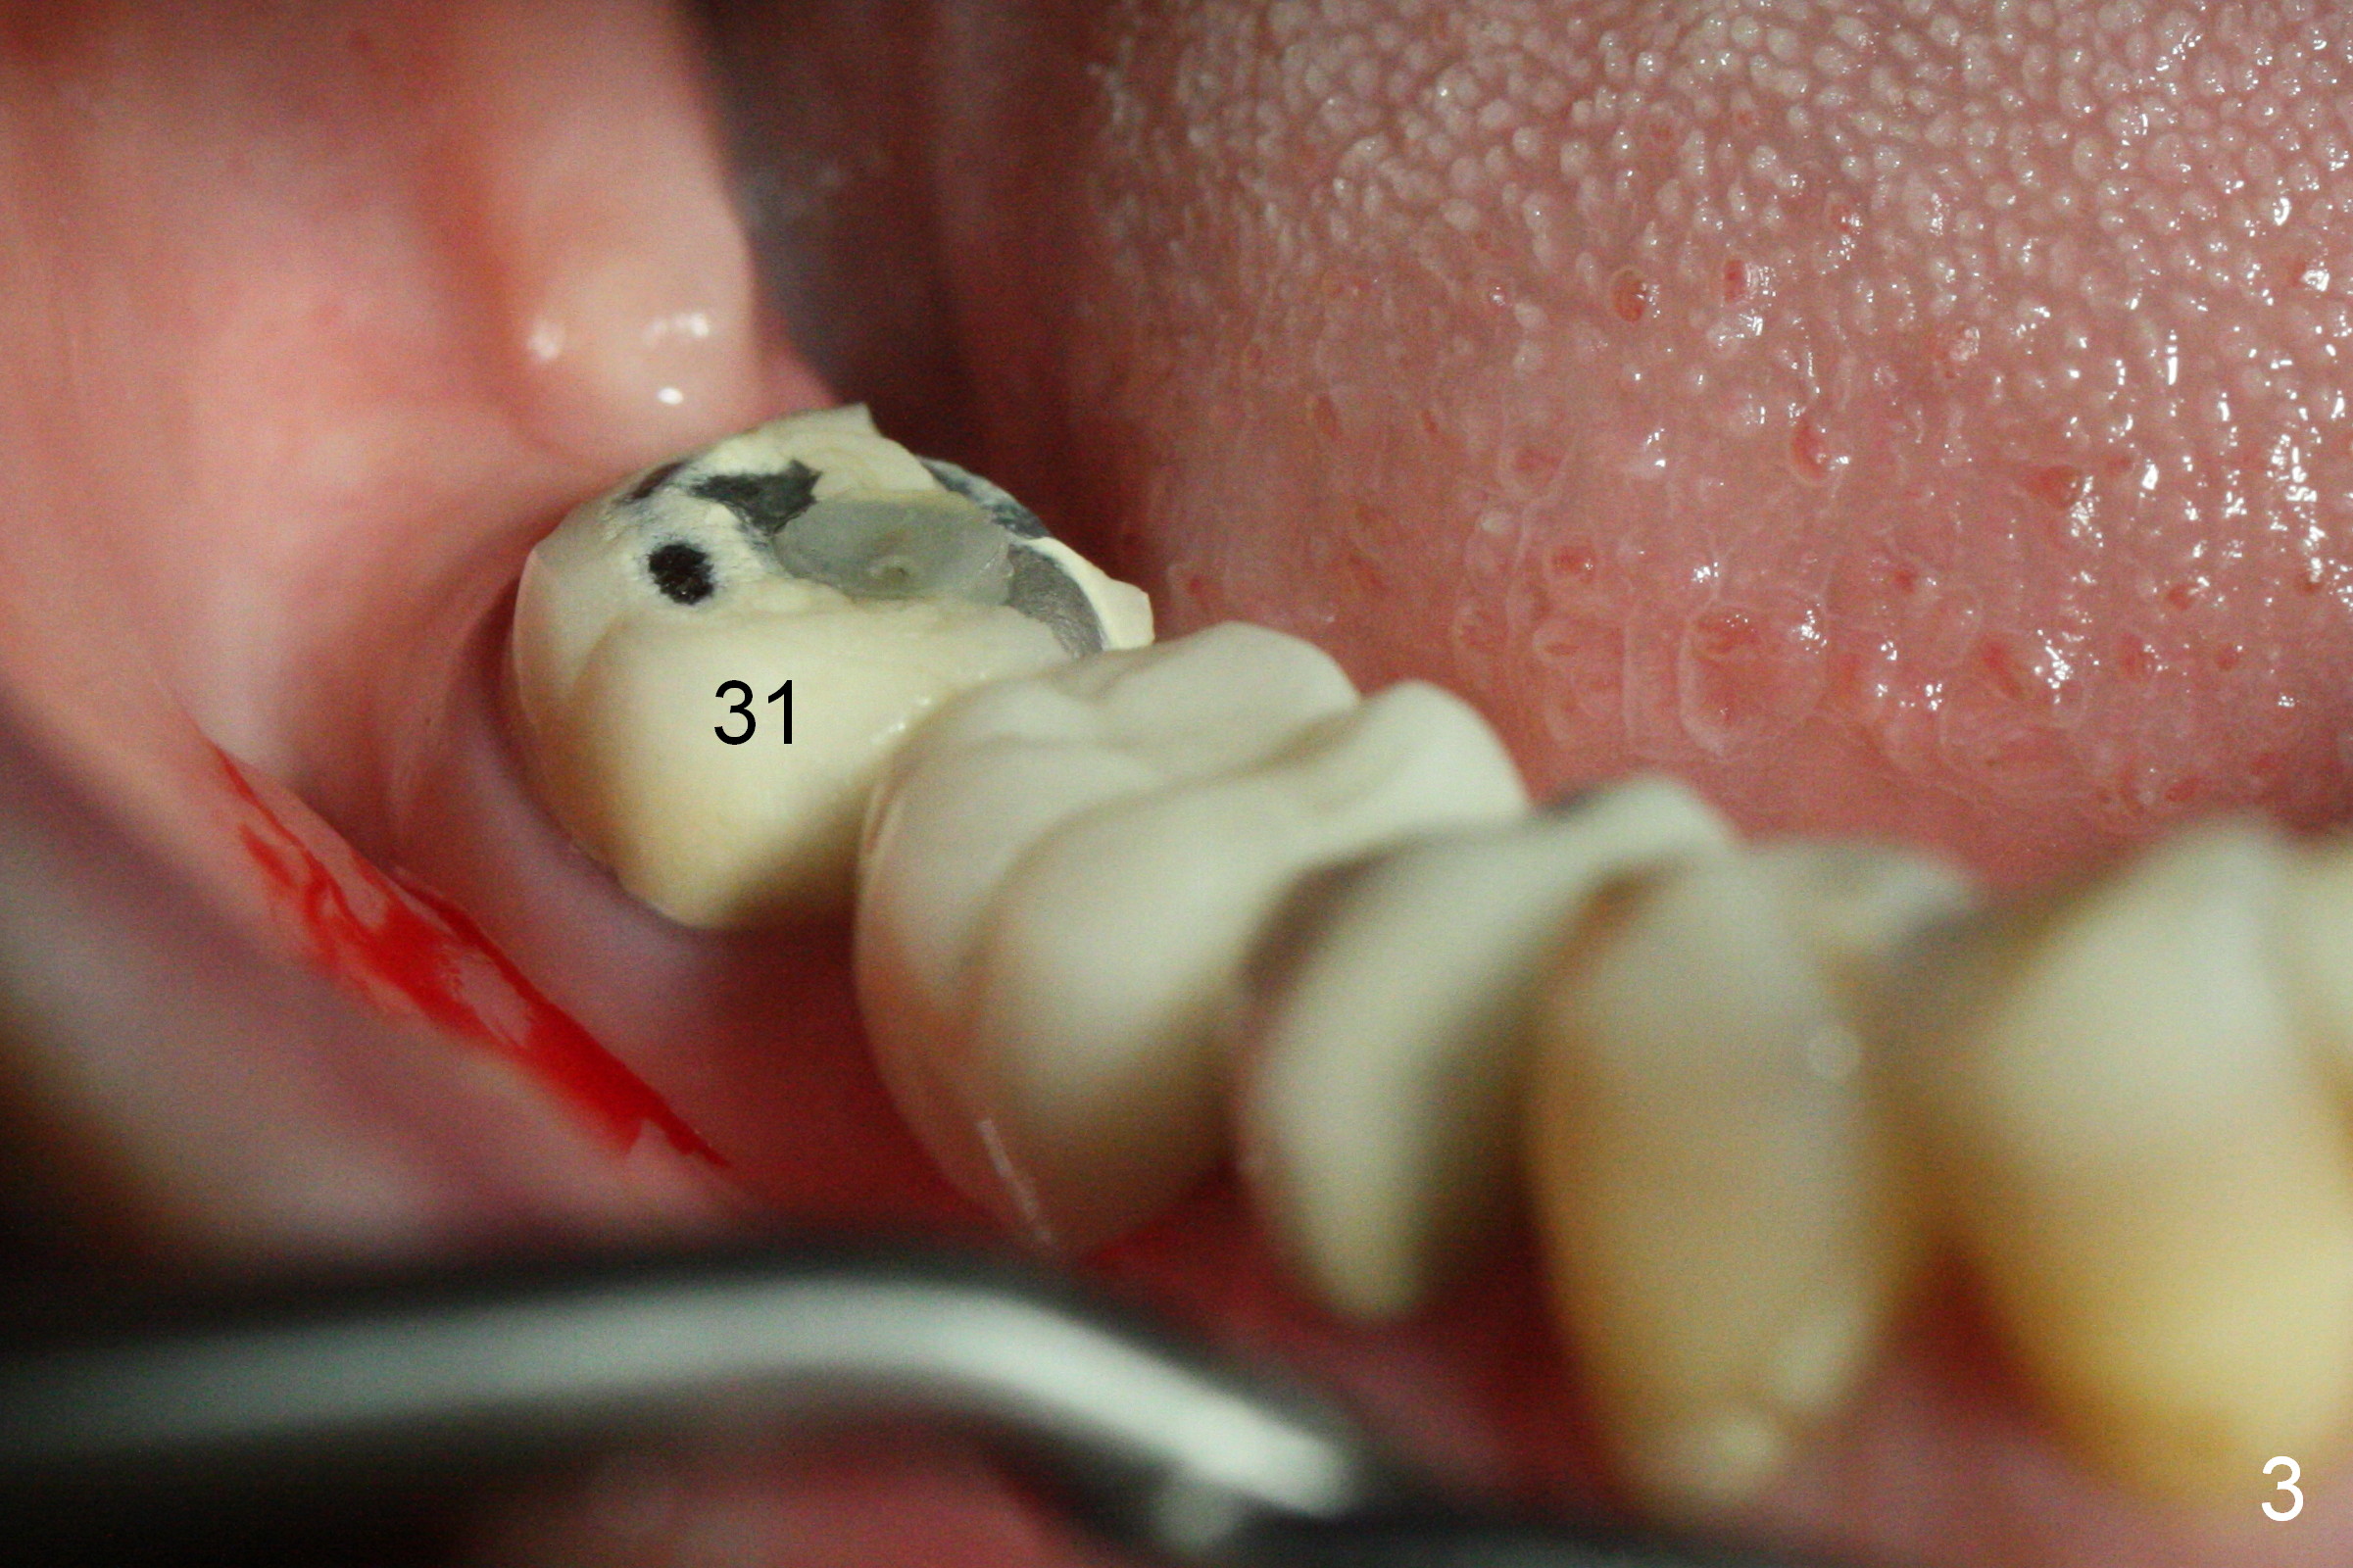

CBCT was taken (Fig.1,2 (P: pontic; S; submandibular fossa)) several months prior to #29 and 31 RCT and #31 porcelain chip (Fig.3). When the bridge is sectioned, the pointed ridge at #30 (Fig.1) is confirmed (Fig.4,5). After flattening the ridge until 6 mm buccolingually (Fig.6 arrowheads), osteotomy is initiated with 1.6 mm drill at 9 mm; there is 2.5 mm clearance from the superior border of the Inferior Alveolar Canal (red dashed line). A 4.5x9(1) mm Magicore is placed with 35 Ncm (insertion torque) after 4.3 mm Magic Drill; a 4.5 mm healing abutment (Fig.7 H). An error occurs because of using 1 mm cuff of the Magicore. Ideally 3 or 4 mm cuff should have been used because of reduction of the ridge by ~ 3 mm (Fig.2). The result of the error is failure of placing the implant at the desirable depth (<9 mm). The coronal threads are exposed and have to be covered by bone graft (autogenous bone and allograft (.5-1.5 mm) (Fig.8 *), followed by collagen dressing. Extra suturing is done to securely close the wound (Fig.9), followed by periodontal dressing (data not shown).